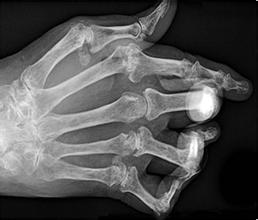

类风湿可以治好吗?类风湿是一种会导致关节疼痛、肿胀,甚至畸形等的关节疾病,使很多人受到了疾病的困扰,为了摆脱这种疾病的困扰,需要进行相应的治疗。那么,类风湿可以治好吗?让…「查看详情」